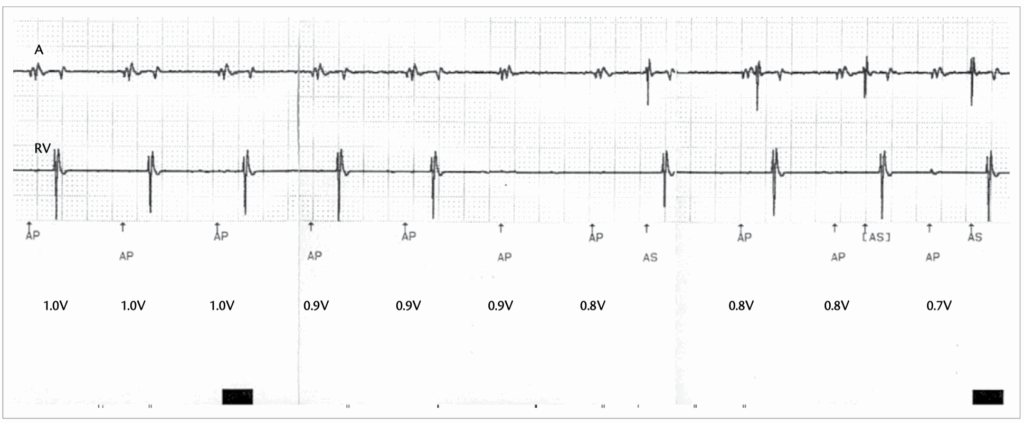

An atrial threshold test was performed in a patient with sinus node dysfunction and normal AV conduction. The test was performed by pacing in the AAI mode and decrementing the atrial voltage amplitude at a pulse duration of 0.4ms

DDI

1 – There is loss of AV synchrony with atrial sensed events (AS) at a constant ventricular pacing (VP) rate 60 bpm (VP-VP 996 – 1000 ms) -> this excludes DDD and VDD.

2 – In DDI mode -> VA interval is triggered after a VP or VS events. AR that fall within the PVARP do not inhibit AP.

3 – AP occurs at the end of the VA interval (800 ms).

4 – AV synchrony is maintained after AP events.